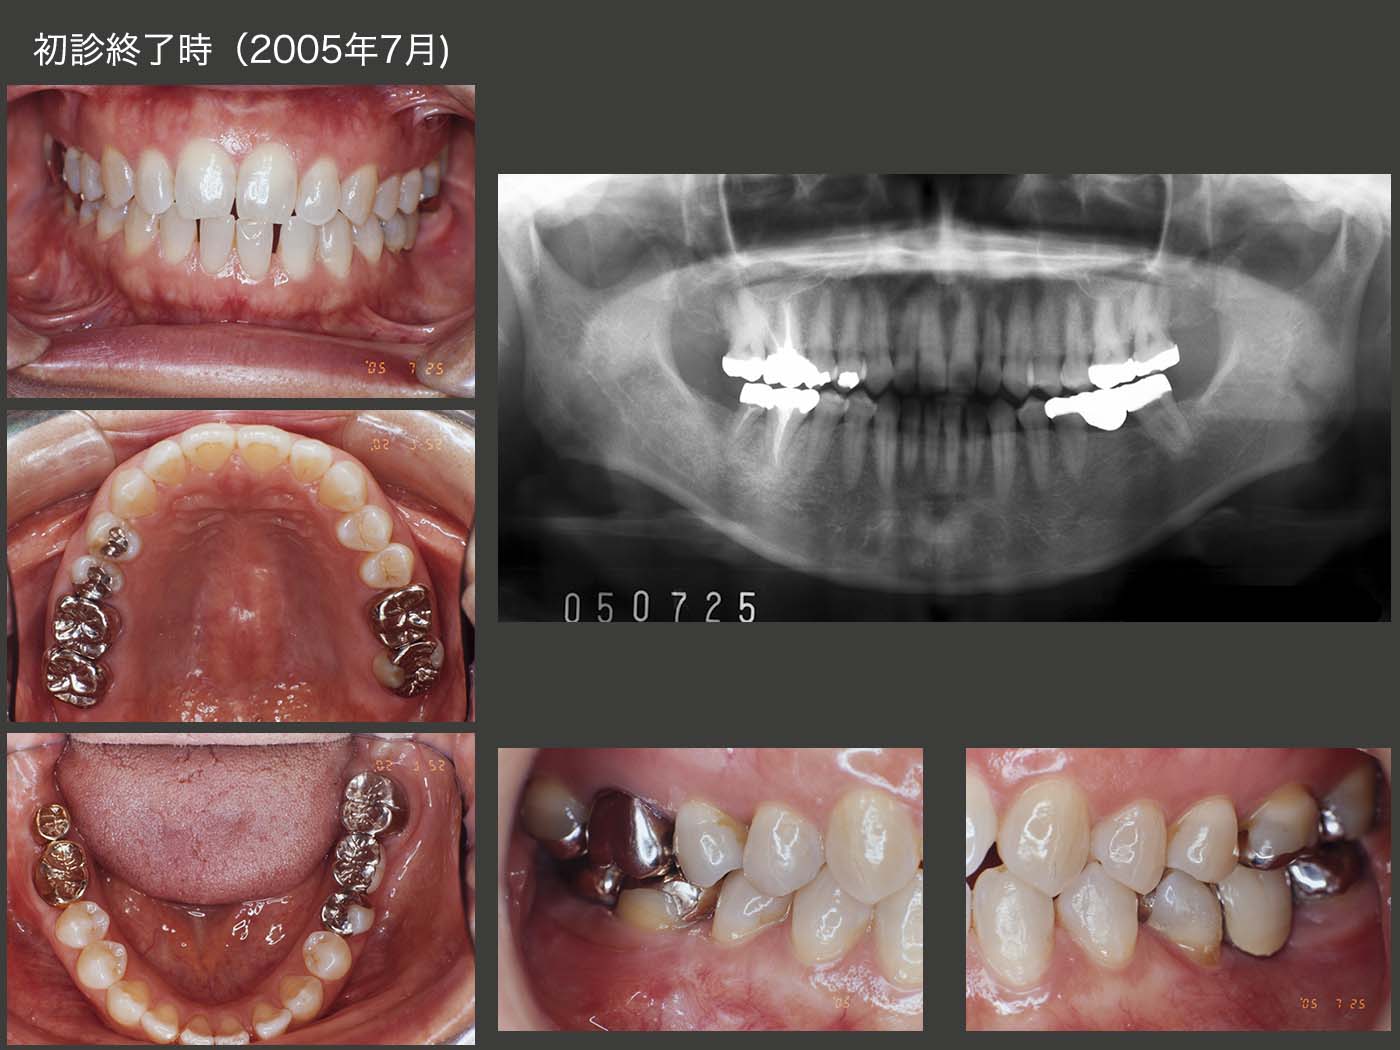

2005年7月,初診終了時の状態.移植した右下6および7は,今なら連結固定するところであるが,当時は暫間被覆冠にて暫く経過を観察して,特に問題がみられなかったため,それぞれを単独冠とした.左下のブリッジについても,保持力の増大のためには左下5の頰側歯質を削去し,フルクラウンにするべきであろう.しかし,保険給付の範囲内となると,理解していても頰側の削去をためらってしまう.実際,ブリッジが将来外れないように頰側を削去するか,あるいは審美性のために残すかを患者さんに選んでもらうと,後者を選択する人が多い.